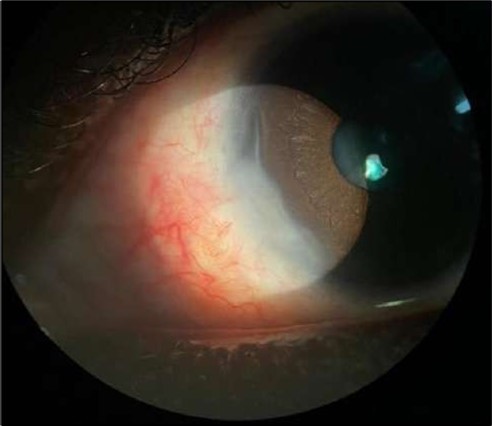

On the current presentation, Snellen VA was 6/6 in the right eye and 6/9 in the left eye, with normal IOP. The left eye demonstrated mild upper lid edema and intense nasal ciliary injection. Slit-lamp evaluation revealed a crescentic area of stromal corneal melting between 7 and 10 o’clock nasally, with overhanging edges and a fluorescein-positive base. No corneal infiltrates were present, and the surrounding stroma remained clear. The anterior chamber was deep and quiet, lens was transparent, pupil was round and reactive & normal posterior segment. Anterior segment optical coherence tomography (AS-OCT) confirmed a localized ulcer, measuring 1324 µm in horizontal width and extending to a depth of 380 μm, compared with an adjacent healthy corneal thickness of 824 µm, corresponding to approximately 46.1% stromal thinning (Figure 1a, Figure 1b, Figure 1c)

Figure 1a.Left eye (OS), on presentation. Slit-lamp image: crescent-shaped peripheral corneal ulceration located nasally, with severe adjacent conjunctival injection, peripheral thinning, and stromal infiltration.